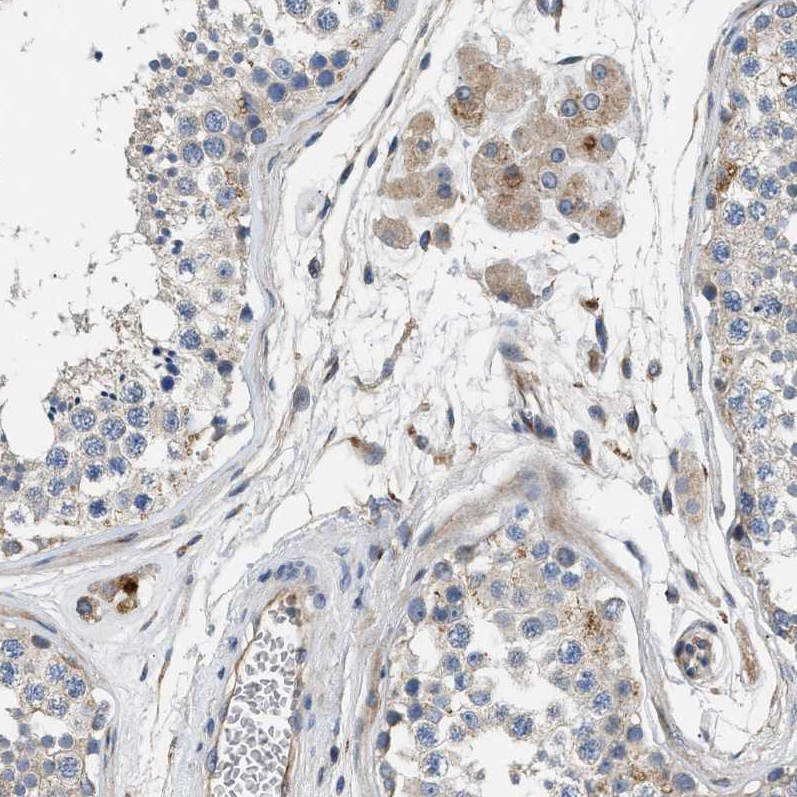

Immunohistochemical staining of human prostate shows moderate cytoplasmic positivity in smooth muscle cells.